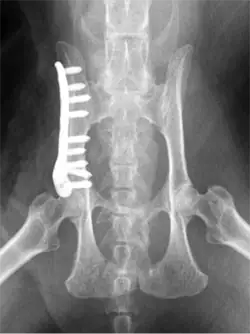

Our dedicated Veterinary Orthopaedic service is available to advise on orthopaedic cases and accept referrals for a full range of orthopaedic problems. Our highly qualified team of experienced and compassionate Specialist Orthopaedic surgeons employ our state-of-the-art hospital facilities to allow the accurate diagnosis of orthopaedic problems using radiography, CT, fluoroscopy, ultrasonography, MRI and arthroscopy.

Our highly qualified Veterinary team of experienced and compassionate orthopaedic surgeons employ our state-of-the-art hospital facilities to allow the accurate diagnosis of orthopaedic problems including: